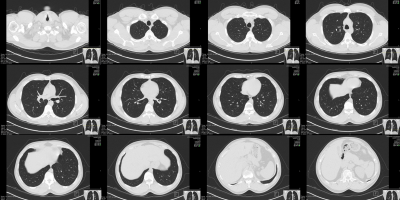

Machine Learning, Medicine, radiology RAD-ChestCT: Publicly Available Multi-Abnormality CT Scan Dataset July 21, 2022

Machine Learning, Medicine, radiology Downloading and Preprocessing Medical Images in Bulk: DICOM to NumPy with Python February 16, 2021